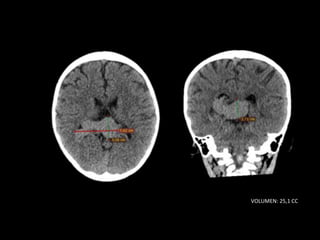

TC SIMPLE DE CRANEO

08/06/2023

VOLUMEN: 25,1 CC

Lesión ocupante de espacio extraaxial

supratentorial a nivel de cisterna cuadrigeminal.

CONCLUSIONES: